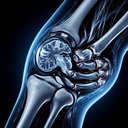

МРТ колінного суглобу

МРТ колінного суглоба – це неінвазивна діагностична процедура, яка використовує магнітне поле та радіочастотні хвилі для отримання детальних зображень структури коліна. Цей метод є особливо корисним для оцінки стану м'яких тканин, таких як зв’язки, м’язи, хрящі та меніски. ### Коли призначають МРТ колінного суглоба: 1...